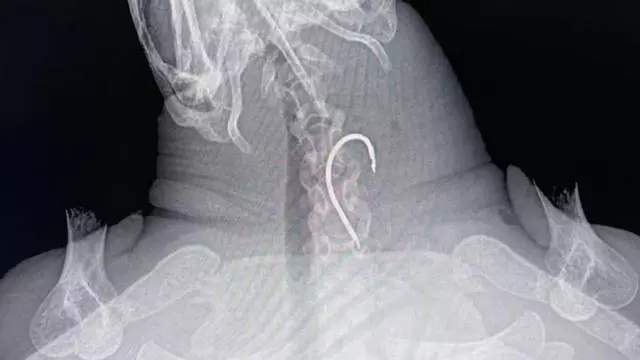

Radiografía del cuello de la tortuga antes de la operación. / Instagram Fundación Palma Aquarium

Durante una revisión mediante rayos X, los especialistas detectaron un anzuelo atrapado en su esófago. La operación, realizada con éxito por el veterinario Juan Ignacio Serra, de la Clínica La Vileta, permitió extraer el objeto sin causar daños graves.